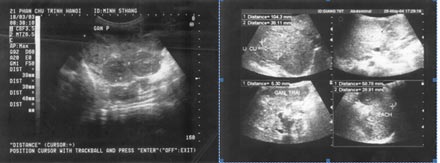

Ở Việt Nam chúng tôi đã sử dụng Curcumin điều trị có hiệu quả rất tốt cho một bệnh nhân u máu nội mô gan ở một trẻ nhỏ 5 tháng tuổi. Bệnh nhân có nhiều u máu, gan kích thước lớn (8 khối u) chiếm trên 60% thể tích gan. Lúc đầu chúng tôi cũng đã liên hệ với nhiều trung tâm nhi khoa nhưng đều có một gợi ý là phẫu ghép gan. Trong lúc tưởng chừng như không còn hy vọng, thử điều trị bằng Curcumin cho thấy các triệu chứng như rối loạn tiêu hoá, vàng da, chán ăn và gan to đã giảm nhẹ, trẻ phát triển tốt về thể lực. Sau 1 năm kiểm tra lại bằng siêu âm cho thấy tất cả các khối u của gan đã mất chỉ còn lại một vài vết sẹo nhỏ.

Đây là trường hợp u máu nội mô gan ở trẻ còn ẵm ngửa lần đầu tiên và duy nhất được điều trị hiệu quả bằng Curcumin được công bố trên y văn thế giới (http://www.ncbi.nlm.nih.gov/pubmed/20582974). Kết quả chứng tỏ Curcumin có tác dụng ức chế tăng sinh tế bào nội mô.

Ảnh siêu âm trước điều trị (18/03/2003) Ảnh siêu âm sau điều trị (05/2004)